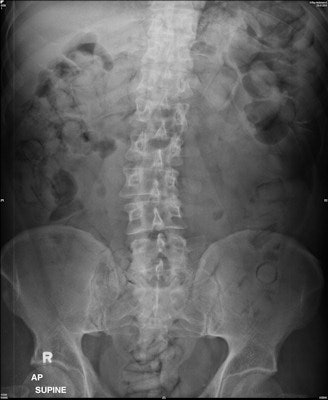

The generally accepted radiological exam is a plain abdominal radiograph in the supine position. However, the detection rate for drug-filled packets is highly variable in the literature, and sensitivities ranging from 58.3% to 90% have been reported. Thus, plain abdominal radiography is considered a flawed screening method for identifying drug mules.

In all confirmed drug carriers, the "double-condom" and "halo" signs (100%) were detected by each radiologist, Rashid and colleagues found.

"These radiological signs occur due to inevitable air inclusion during manufacturing of drug packets, which creates the specific double-condom sign if the pack is projected longitudinally or the halo sign if it is imaged transversely," they wrote. "However, the 'rosette' sign (due to trapped air at the twisted end of a pack) is not easy detectable on plain radiograph and was only reported in a single (6.25%) case by one radiologist in the experienced group."

Other signs include the "tic-tac" and "parallelism" signs, which are created by the parallel arrangement of longitudinal packs within the large bowel (seen in three cases). Suspicious gas formation in the rectum was reported in two cases by one radiologist in the inexperienced group, but these cases were confirmed to be negative.

In terms of shape, nearly all the drug mules (93.75%) ingested typically shaped longitudinal or tubular body packs wrapped in plastic or condoms. The longitudinal or tubular shape was observed in each case (100%) on imaging, whereas the round shape was observed in one (6.25%) case by all radiologists.

In terms of size, the average length of the longitudinal packs was 4.93 cm (range, 2.5-6.8 cm; median, 5.0 cm) and the width was 2.12 cm (range, 1.4-3.1 cm; median, 2.1 cm). The round drug packs measured 2.0 cm to 5.6 cm in diameter, with an average diameter of 3.18 cm (median, 2.5 cm). The shapes and size measurements on DR were correct according to the measured packs in the feces.